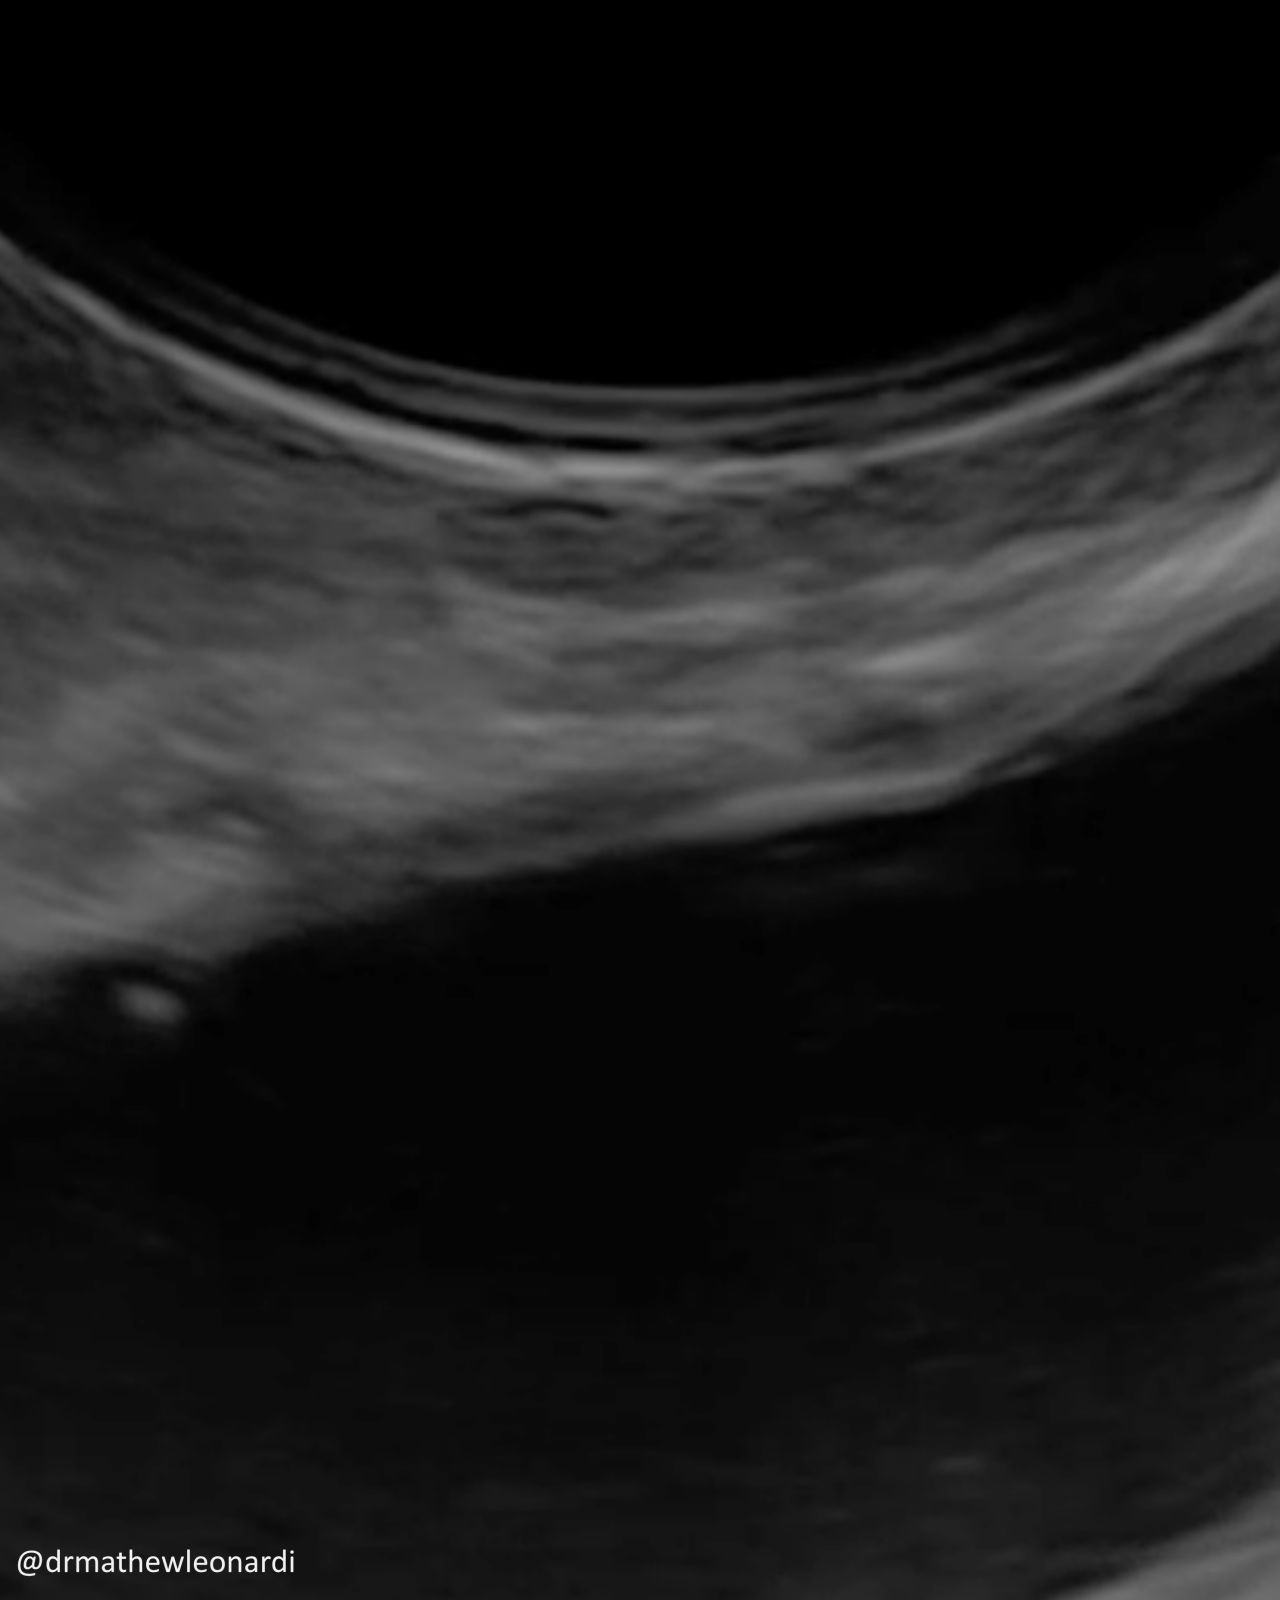

“Endometriosis does not have one single appearance, and that is part of why it is so often missed.

In this carousel, I’ve included a range of endometriosis lesions across different disease types and locations, including superficial disease, ovarian disease, and deep endometriosis involving areas such as the bowel, bladder, uterosacral ligaments, peritoneum, vagina, and ovary. A few are deliberately difficult because real-life recognition is not always straightforward.

As you go through the images, pause on each one and ask yourself:

What would make this easy to miss?